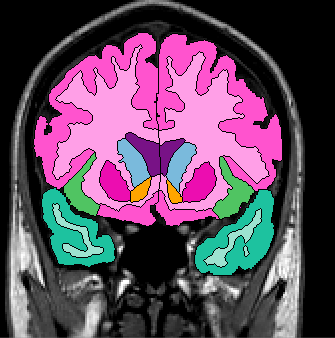

General Description

The cerebral exterior is the border between the subarachnoid CSF and neural

tissue, and should correspond to the pia mater. Thus, the cerebral exterior

separates brain from non-brain, cerebrum from cerebellum, and divides the brain

into its two hemispheres. The brain lobes are the four areas of cerebral exterior

including the frontal, parietal, temporal and occipital lobes. Each brain lobe

has distinct physiological functions. The brain lobe borders are distinguished

by specific sulcal and gyral borders.